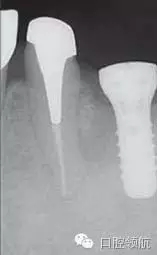

圖2是右側(cè)種植體植入后,左下磨牙缺損部診斷用導(dǎo)板戴用時的曲面斷層影像。拔牙后6個月,在預(yù)定植入部位有若干不透明的影像。

圖2 左下磨牙缺損部植入前的曲面斷層影像。